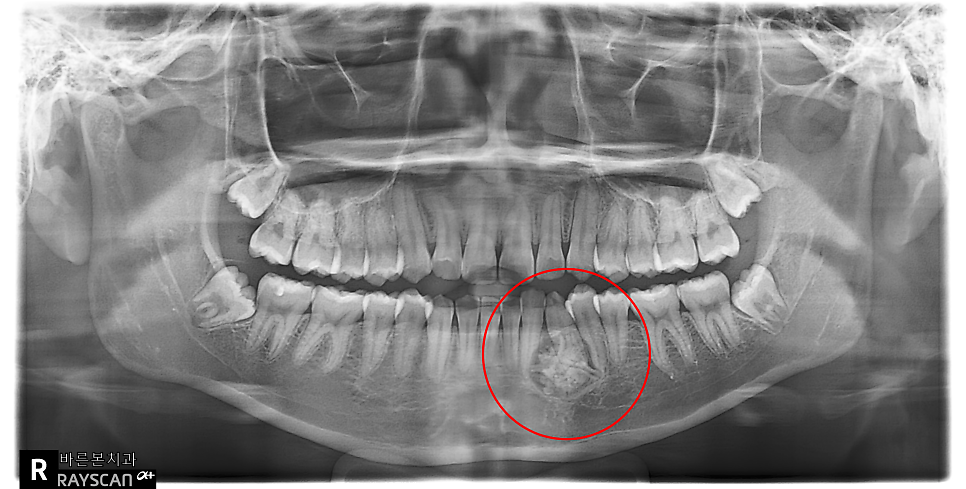

원장실에서 X-ray를 봤을때

“와 크다” 라고 생각하며

저 역시 긴장을 하고 학생을 처음

진료를 했던 기억이 납니다.

빨강색동그라미를 보면 치아 사이에

뭔가 별처럼 생긴 거대한 구조물이 관찰됩니다.